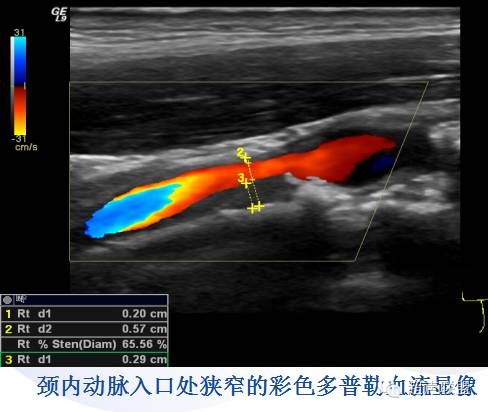

2、CDFI及PW:(注意检测双侧颈动脉血流频谱)

CDFI见动脉狭窄所致湍流,闭塞者无血流信号。

PW可见外周动脉狭窄的频谱特征,主要指标有PSV、EDV、PSVICA/PSVCCA。(狭窄程度判断见下表)

颈内动脉ICA狭窄诊断标准:

ICA狭窄程度 | 管壁斑块 | PSVICA(cm/s) | EDVICA(cm/s) | PSVICA/PSVCCA |

正常ICA | 无斑块 | < 125 | < 40 | <2.0 |

狭窄<50% | 有斑块或内膜增厚 | < 125 | < 40 | <2.0 |

50—69% | 有明显斑块 | 125-230 | 40-100 | 2.0-4.0 |

>70%,但不到接近闭塞 | 有斑块伴有管腔狭窄 | >230 | >100 | >4.0 |

接近闭塞 | 可见斑块,CDFI显示管腔明显狭窄 | 高、低或探不到血流信号 | 不定 | 不定 |

完全闭塞 | 2DE见不到管腔, CDFI无血流信号 | 探不到血流信号 | 无 | 无 |

注:CCA血流速度频谱:取样点在分叉处以下4cm;SV置于血管中心轴线上;Doppler角度30-60度。